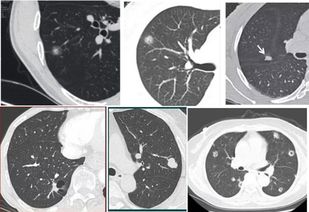

肺结节为小的局灶性、类圆形、影像学表现密度增高的阴影,可单发或多发,不伴肺不张、肺门肿大和胸腔积液。

孤立性肺结节无典型症状,常为单个、边界清楚、密度增高、直径≤3cm且周围被含气肺组织包绕的软组织影。

1、肺部小结节一般是在体检的时候发现,肺部CT显示肺部类圆形病灶,肺部小结节的种类,分为孤立性结节和多发性结节,肺部结节有的可以自行消失,有的不会消失,局部病灶直径大于3cm者称为肺肿瘤。